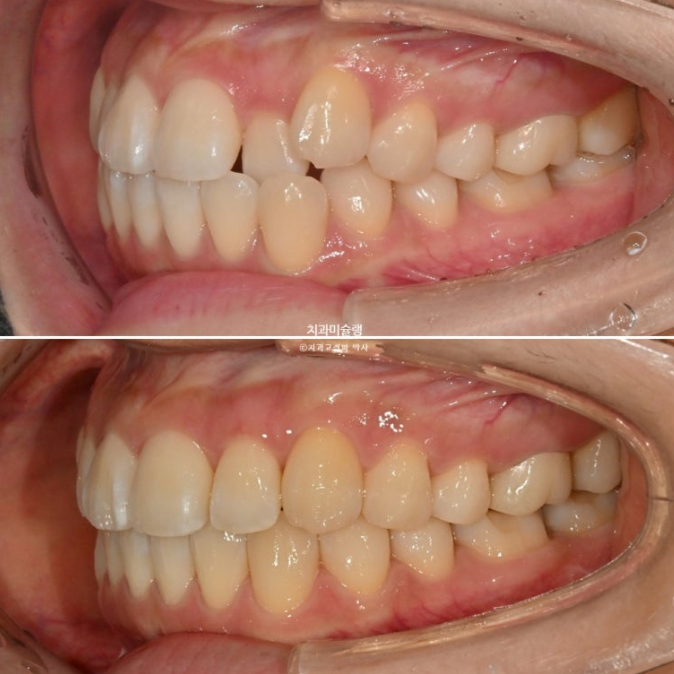

송곳니 덧니와 반대교합이 있는 증례에서 어금니 교합이 좋다면 인비절라인 라이트로도 좋은 결과가 나옵니다.

중심선 불일치, 덧니, 측절치 반대교합을 인비절라인 라이트로 치료한 증례입니다.

중심선 불일치, 덧니, 반대교합 등이 보입니다.

절단교합도 보이고

앞니쪽은 뒤죽박죽이나 그에 비하면 어금니 교합은 아름다운 1급 교합관계를 보입니다.

이제 전후비교 볼게요. 총 치료기간은 9개월입니다.

25.03~25.12